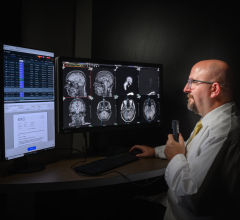

The IMPAX MA3000 Diagnostic Station is DICOM compliant and supports rapid and simultaneous display of multimodality images. It incorporates a data management system that automatically routes relevant data (e.g., DR mammography, breast MRI, ultrasound) based on a variety of user-definable criteria including modality, patient and referring physician. Relevant prior exams can be pre-fetched from the archive management system and sent automatically to the IMPAX MA3000 station. Radiology results from the RIS can be displayed simultaneously when available. Review and comparison of images can be defined per user and per modality.